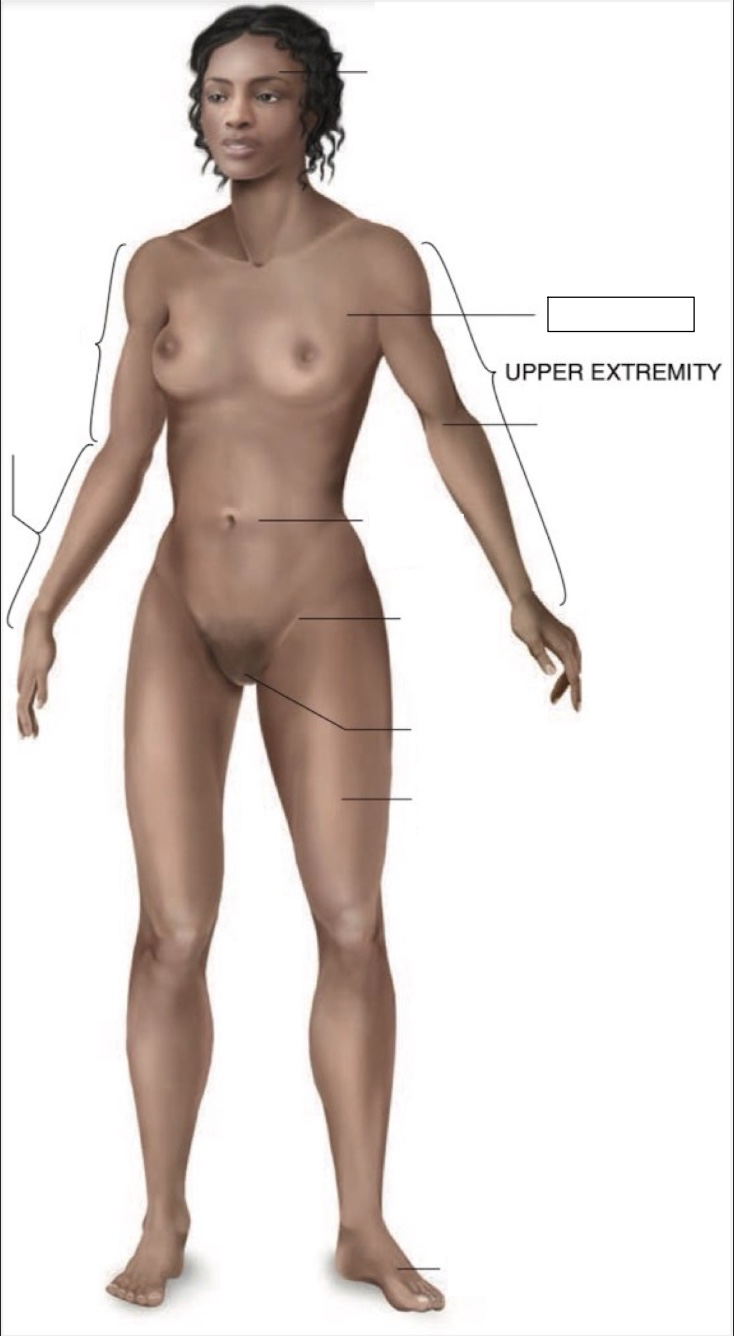

Cranial region

thoracic region

umbilical region

inguinal region

genital region

femoral region

dorsum of foot

arm

forearm

cubital region

midsternal line